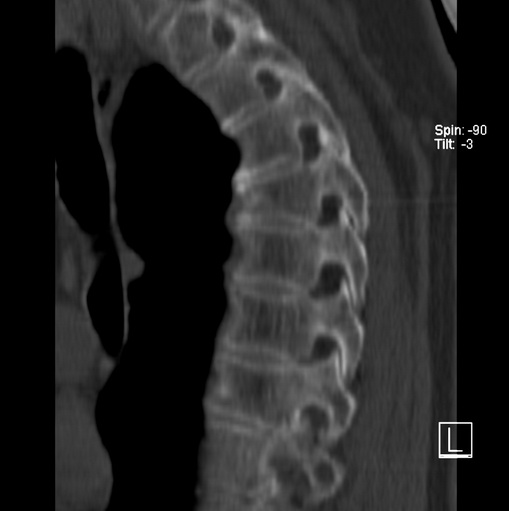

标题: CT25377:脊柱有无压缩骨折?

女、73、胸痛、胸闷3个月,无明显外伤病史,x线疑t4、t7陈旧压缩骨折,ct未经明显骨折,请问结论如何报?

老年女性病人,骨质稀疏,有些驼背,t4明显变扁,t7略变扁,椎体边缘无中断,骨小梁排列正常,无嵌插所致致密线。结合无明显外伤史,考虑老年骨质稀疏,慢性压缩改变,正如老年人骨质稀疏椎体呈双凹改变一样。我考虑报:老年骨质稀疏,t4、t7楔形变,脊柱曲度改变(驼背).敬请大家指教。

1)多个胸椎陈旧性压缩性骨折。2)胸椎普遍性骨质疏松。3)胸椎退行性改变。

1)多个胸椎陈旧性压缩性骨折[骨质疏松所致]。2)胸椎普遍性骨质疏松。3)胸椎退行性改变。